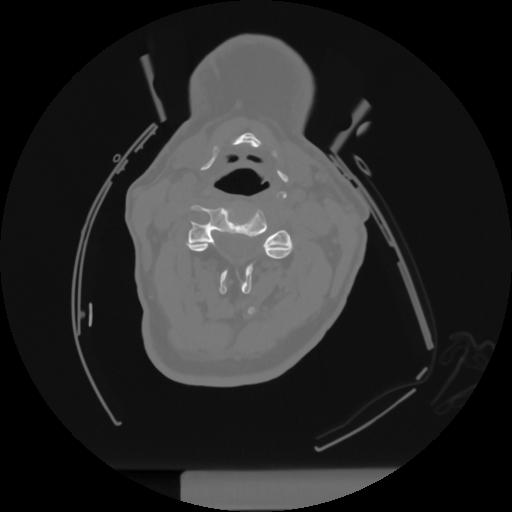

12 P.BLANDAS,,Vol,0.5,P.BLANDAS,,